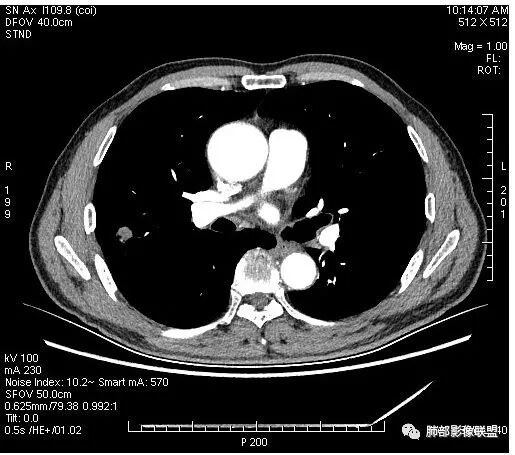

晨读:男,67岁,体检发现右肺结节。近圆形,支气管及伴行血管进入结节,进入结节后支气管堵塞,血管走形尚自然,结节内血管边缘凹凸不平。远端边缘见毛刺(软毛刺?)及分叶。见胸膜牵拉。实变中见空洞。整体膨胀感不明显。考虑炎性肉芽肿可能,隐球菌病可能性大。注意鉴别鳞癌、结核。

虽然良恶性征象都有,但是这个病灶增强后坏死比较明显,如果是恶性:腺癌这样大小的结节坏死很少见,只有低分化腺癌可以坏死,但是低分化腺癌这种大小一般会有周围转移表现(叶间胸膜结节,癌淋或者淋巴结明显肿大),如果是鳞癌,收缩力,坏死情况以及没有支气管截断都不太支持,而且结节远端有几个小结节样改变,大家可能认为是血管,但我觉得应该是卫星灶。所以觉得隐球可能较大。壁胸膜的牵拉线也没有引起胸膜凹陷,比较纤细,至于病理中的丝状物不一定是真菌菌丝。

这个大部分边缘稍微偏平直一点,血管走行非常自然,包括里面的空泡征样的,影子很干净,边界很光滑,都是些炎性特点。

1.右肺上叶后段类圆形结节影,密度不均,有坏死空洞,坏死比较彻底,内外壁都较清楚。

4.病灶轻到中度强化。病灶内血管走行较完好,病灶旁血管局部显示粗大。

5.支气管关系不确定。

1.病灶整体太圆,没有深分叶,没有粗短毛刺,收缩明显乏力,强化不显著等等缺乏典型肺腺癌的影像学特征。腺癌如此小病灶出现空洞更是匪夷所思!

2.肺鳞癌易坏死,可病灶如此小即出现影像学上可见的彻底的坏死空洞也非常少见。

病灶内“旁若无人”的血管走形也让人难以理解。而该疑问也存在于结核病灶的辨析当中。

病灶相对局限,或偏安肺野一隅,小病灶带空洞,最常见的还是感染。

1.结核是常见的,坏死也够彻底,有卫星灶。疑问在于血管为什么不受累?

2.其他的慢性炎症。边界清楚符合慢性。慢性肺脓肿、隐球菌感染、奴卡菌感染等等都可以。可惜缺乏病原学依据。